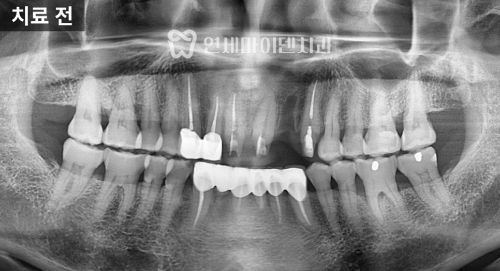

치료 전 상황

이미 앞니 하나가 발치된 상태였던 이번 케이스는

기존 브릿지 보철 치료로 인해 스트레스가 있었고,

'자연스러운 임플란트'에 대한 요구가 명확했습니다.

3급 부정교합 진단

방사선 사진을 분석해 보니

위턱보다 아래턱이 발달한 3급 부정교합,

흔히 '주걱턱'이라고 하는 상태였습니다.

아래 앞니의 각도가

정상치보다 훨씬 작은 68.7도로

안쪽으로 쓰러져 있었습니다.

정면 방사선에서는

위턱과 아래턱의 폭 차이가 정상보다 훨씬 커서

위턱이 약 10mm 이상 좁은 상태가 확인됐습니다.

파노라마 방사선에서도 치근 흡수나 잇몸 손상 없이

안정적으로 마무리되었습니다.